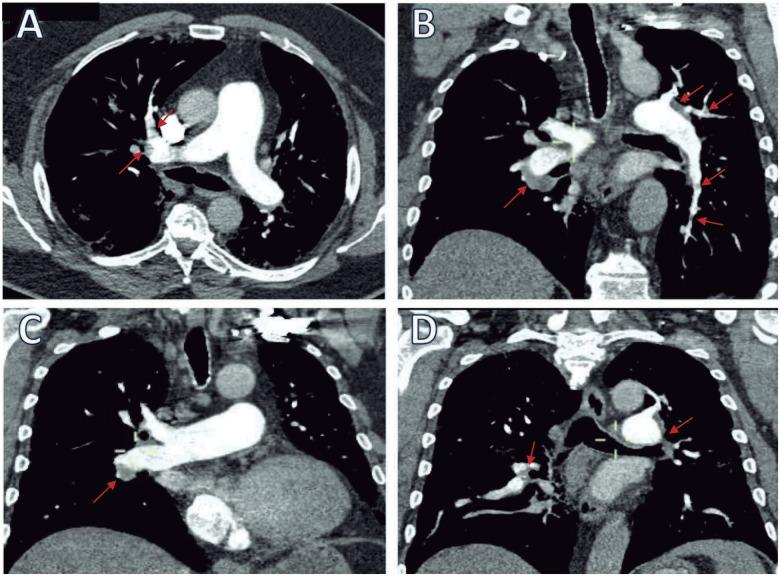

We present a case of a 69-year-old man with a clinical presentation of massive-like pulmonary embolism (PE) overlapping with severe COVID-19 pneumonia. The diagnosis was made based on hypotension, severe oxygen desaturation (33%), and right ventricular dysfunction (RVD). We used alteplase and low-molecular-weight heparin, obtaining immediate clinical improvement. Also, we identified an extremely elevated D-dimer (31.2 mcg/mL), and computed tomography pulmonary angiography (CTPA) revealed an unexpected low thrombus burden and a crazy-paving pattern. Considering this, we decided to discontinue the alteplase. Therefore, the mechanisms of pulmonary hypertension and RVD could be multifactorial. Despite the patient's respiratory status worsening and ongoing mechanical ventilation, biomarkers kept lowering to normal ranges. It appears a favourable outcome was related to early PE diagnosis and a multimodal therapeutic approach.

Physicians in the ER should be warned about extremely high D-dimer measurements and severe oxygen desaturation as possible markers of severe COVID-19 pneumonia in patients with high-clinical suspicion of PE. Although ESC guidelines recommend immediate reperfusion in cardiogenic shock secondary to PE, we suggest initial CTPA in patients with high-clinical suspicion of severe COVID-19.